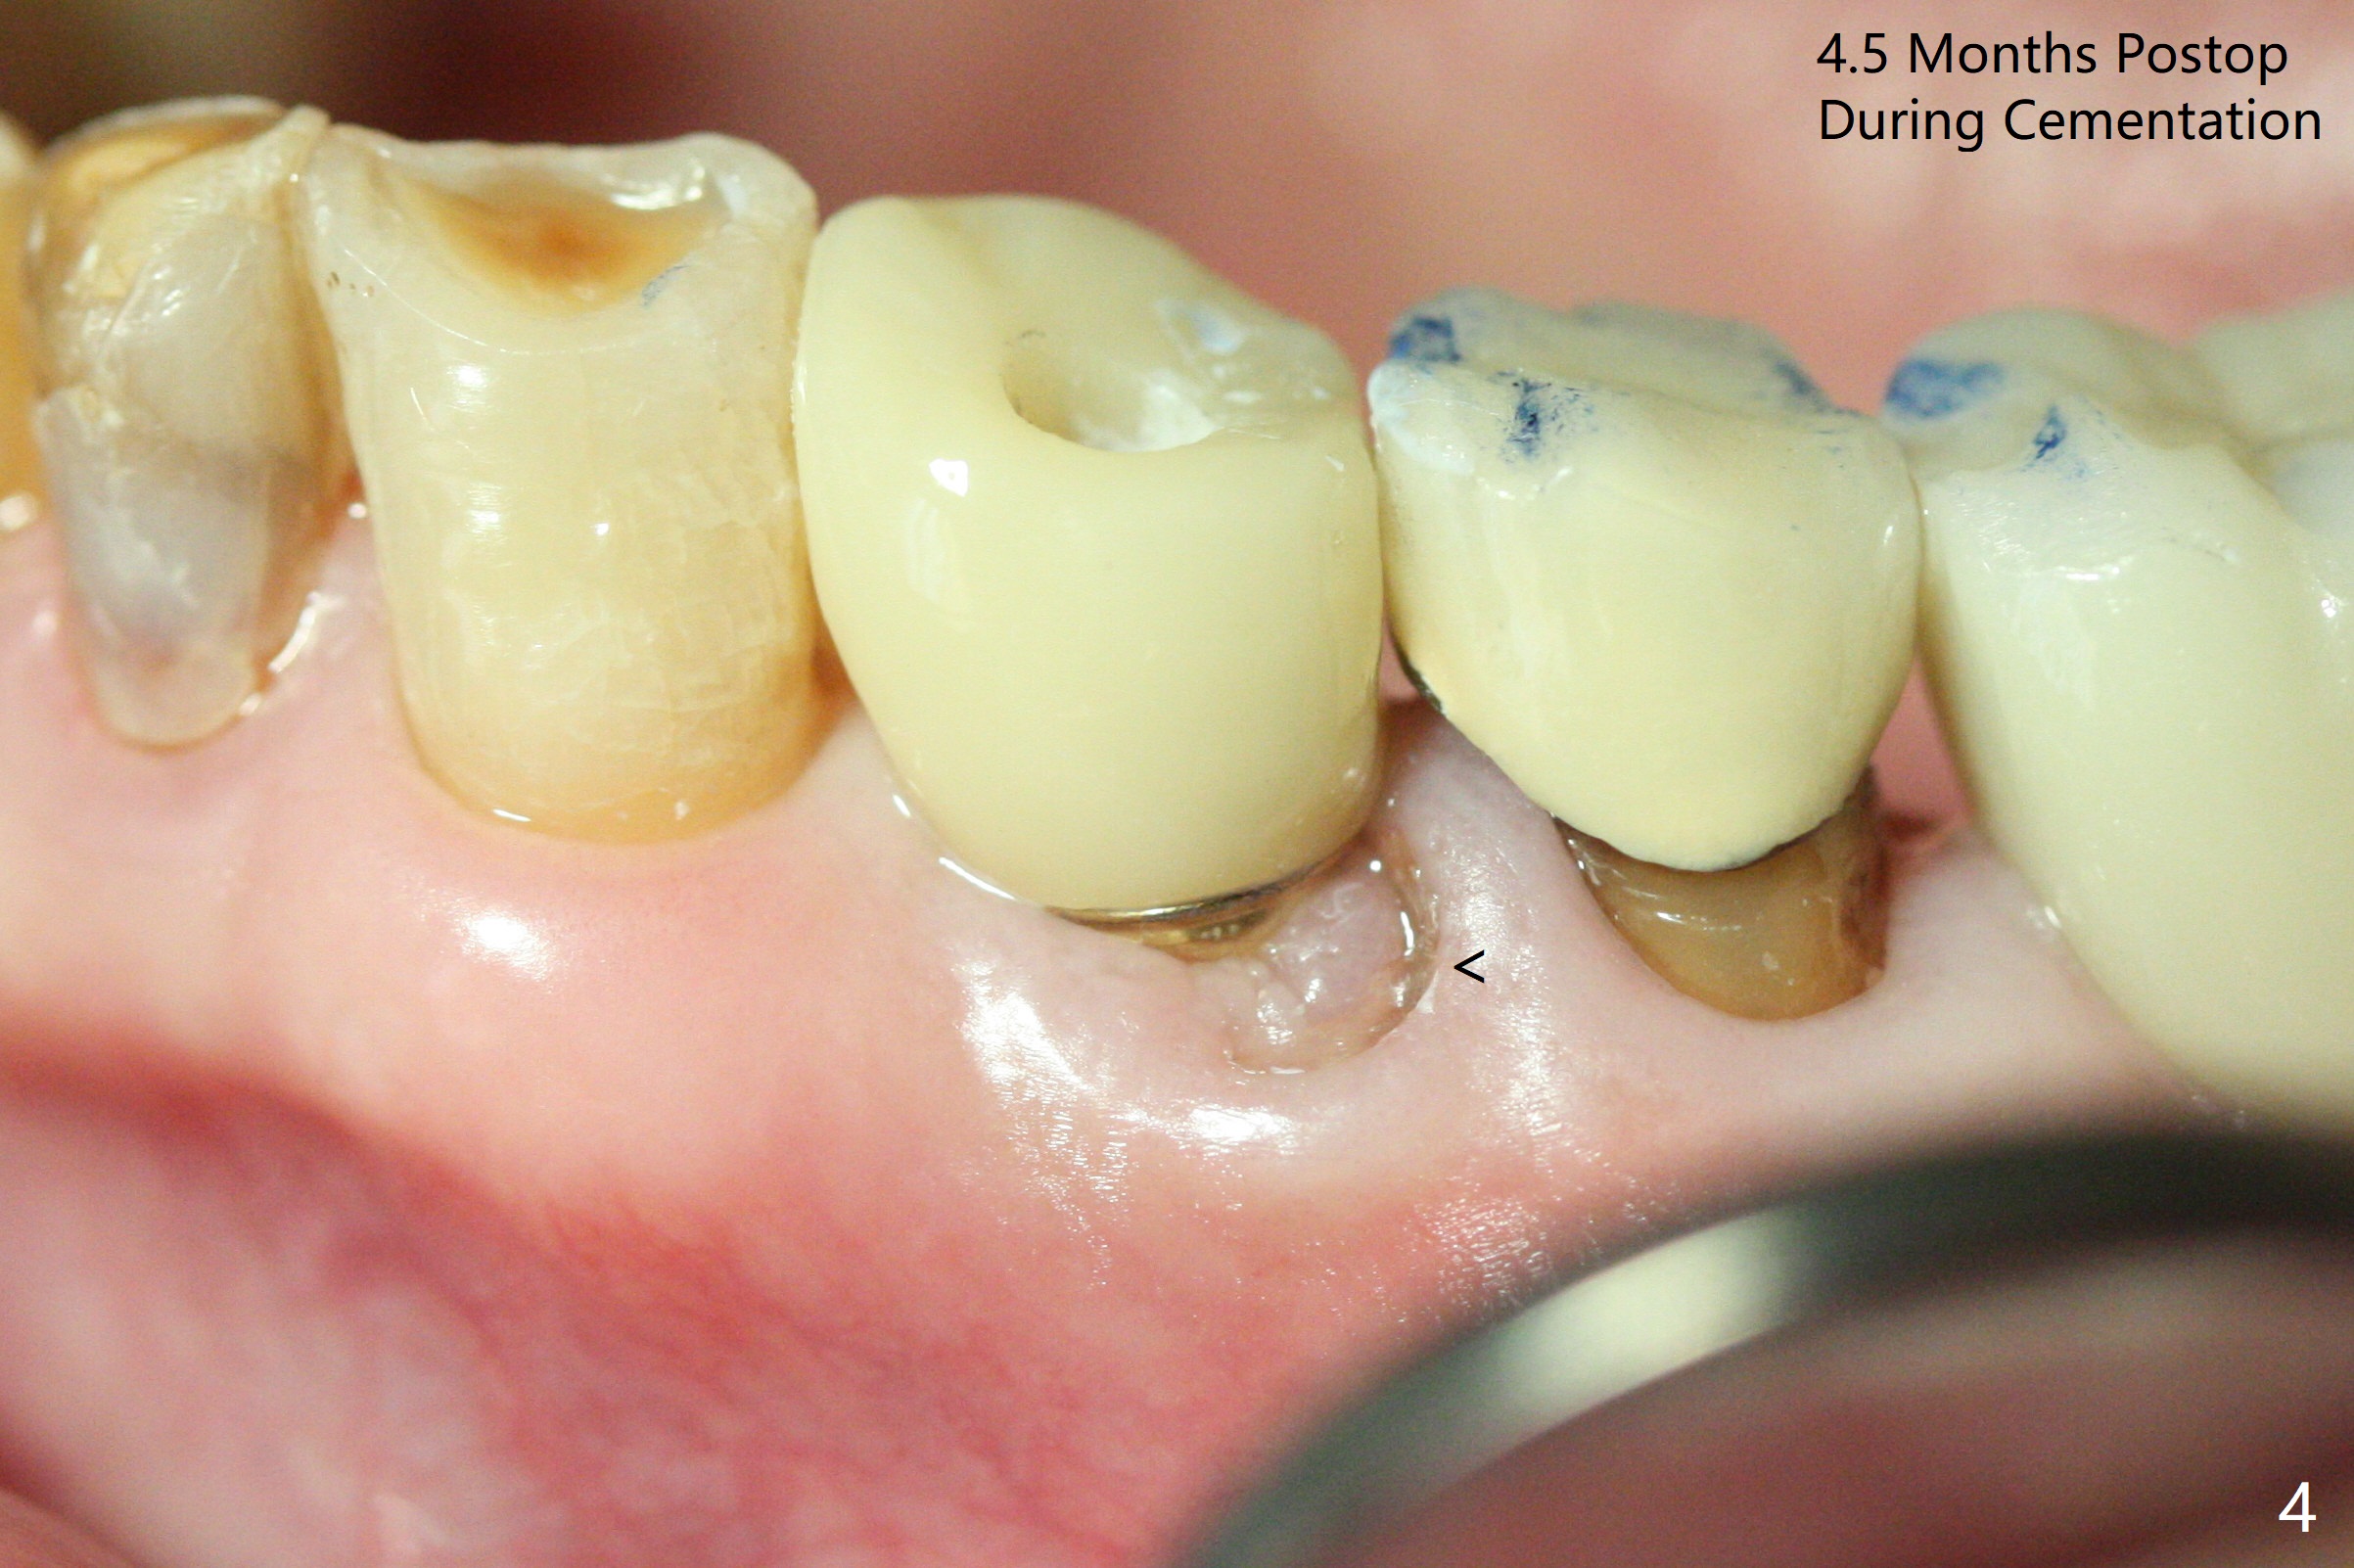

Extraction of the fractured tooth at #21 is as difficult as #19 (requiring incision). Because of the long root and hemorrhage, the apex of the tooth (Fig.1 black *) and a thin layer of the buccal shield (white *) remain when osteotomy is initiated. Due to hard bone, a 3.8x11.5 mm implant achieves insertion torque of ~35 Ncm (Fig.2); with placement of a 4.5x4(3) mm abutment, an immediate provisional is fabricated. There is limited remaining space for bone graft. The patient will return for final restoration 4 months postop; the buccal plate will be expected to have not collapsed! The implant seems to be osteointegrated, while the root piece (socket shield *) is exposed 4 months postop (Fig.3). The socket shield seems to be harmless, difficult to trim without local anesthesia and associated with no buccal plate concavity (Fig.4,5 <). With socket shield at #21, the crown looks normal, whereas the one at #19 without socket shield looks long, suggesting vertical bone loss early postop (before restoration, Fig.6).没有牙根处,角化龈少(图七,与术前(图八)对比)。